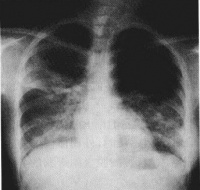

胸部X线检查早期可无异常,一般1周内逐渐出现肺纹理粗乱的间质性改变、斑片状或片状渗出影,典型的改变为磨玻璃影肺实变影。可在2-3天内波及一侧肺野或两肺,约半数波及双肺。病灶多在中下叶并呈外周分布。少数出现气胸纵隔气肿。CT还可见小叶内间隔和小叶间隔增厚(碎石路样改变)、细支气管扩张和少量胸腔积液。病变后期部分患者肺部有纤维化改变。

SARS

SARS2